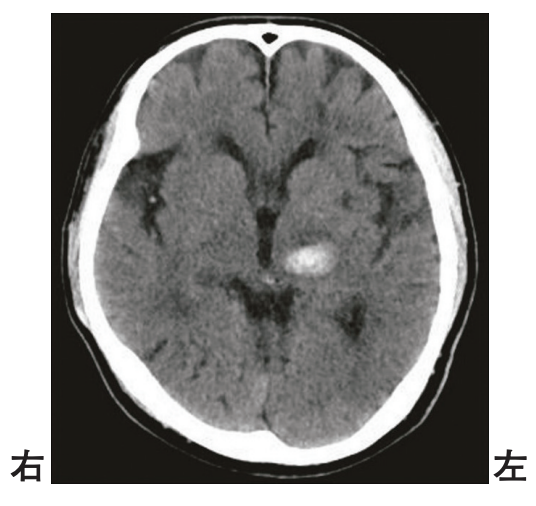

頭部CTを別に示す。

出血部位はどれか。

• 後頭葉皮質下

• 頭頂葉皮質下

• 尾状核

• 被殻

• 視床